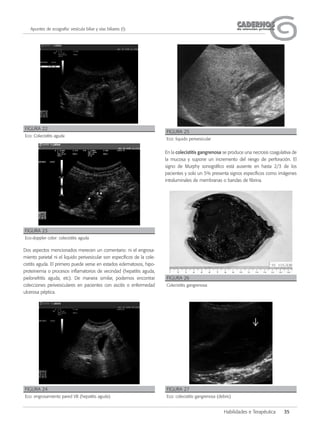

Dos aspectos mencionados merecen un comentario: ni el engrosa-

En la colecistitis gangrenosa se produce una necrosis coagulativa de

la mucosa y supone un incremento del riesgo de perforación. El

signo de Murphy sonográfico está ausente en hasta 2/3 de los

pacientes y solo un 5% presenta signos específicos como imágenes

intraluminales de membranas o bandas de fibrina.

FIGURA 22

Eco: Colecistitis aguda

FIGURA 23

Eco-doppler color: colecistitis aguda

FIGURA 24

Eco: engrosamiento pared VB (hepatitis aguda)

FIGURA 25

Eco: liquido perivesicular

FIGURA 26

Colecistitis gangrenosa

FIGURA 27

Eco: colecistitis gangrenosa (debris)